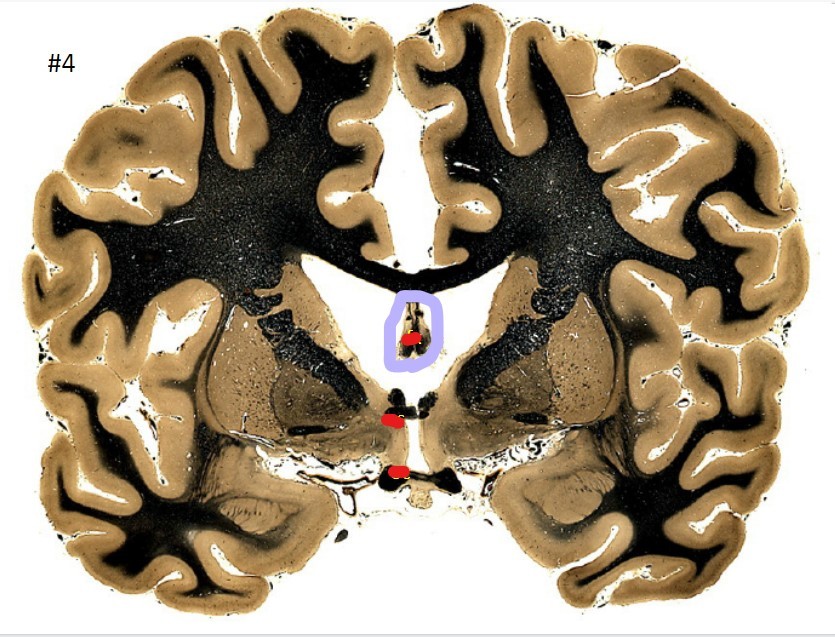

what is the circled area (#4)?

the fornix

the anterior commissure

the optic chiasm

the putamen

the globus pallidus

the internal capsule

the caudate nucleus

the corpus striatum